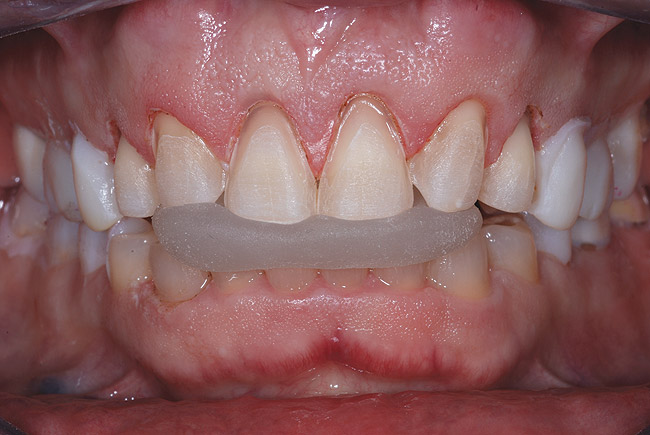

Următorul pas logic era determinarea poziţiei muchiei incizale ideale a incisivilor centrali cu buzele în repaus, prin efectuarea unui mock-up intraoral din compozit. Compozitul fluid reprezintă o bună opţiune pentru adăugarea provizorie la muchiile incizale şi/sau la acoperirea ţesutului pentru testarea diferitelor schimbări, vizualizarea rezultatelor proiectate şi pentru a obţine acceptul pacientului. Prin adăugarea compozitului la ariile gingivale şi incizale ale dinţilor 1.1. şi 2.1., s-a stabilit o nouă formă incizală pe care pacientul a aprobat-o. S-a verificat fonetica şi afişarea corespunzătoare a unei lungimi de 2-3mm, cu buzele în repaus9 (fig. 2).

Cu mock-up-ul fixat pe dinţii laterali, în scopul de a menţine dimensiunea verticală şi relaţia interocluzală, s-au efectuat preparările dinţilor frontali superiori şi inferiori cu utilizarea pieselor de mână electrice şi a instrumentarului diamantat. Raportarea constantă la ghidajele de reducţie permite o reducere dentară de mare precizie.10,11 Incisivii inferiori au constituit o situaţie cu preparare minimă, cu abordarea suplimentară numai a contururilor faciale şi a celor incizale. Înregistrarea unei ocluzii frontale s-a obţinut cu ajutorul unui material acrilic rigid fotopolimerizabil (fig. 4).